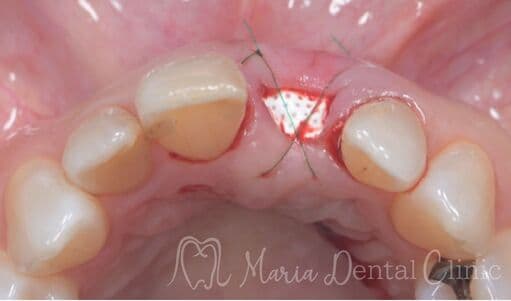

結合組織移植術(CTG)により機能および見た目を改善

抜歯後に生じた歯肉の陥凹は、見た目の不調和や清掃性の低下を招くことがあります。本症例では、ブリッジ治療に先立ち、結合組織移植術(CTG)を行い、失われた歯肉のボリュームと自然なラインを回復しました。歯肉の形態を整えることで、審美性と機能性の両面から調和のとれた補綴治療を実現しています。

治療内容 結合組織移植術(CTG)

治療期間 6ヶ月(外科処置から最終補綴物が入るまで)

治療回数 1回(他、抜糸、経過観察等を除く)

治療費用 165,000円〜(税込)

症例から言えること

審美的で長期的に安定した補綴治療には、生理的な歯肉形態の回復が欠かせません。CTGにより歯肉の厚みを再建することで、ポンティック周囲の清掃性が向上し、自然な見た目も得られます。歯肉の凹みやブリッジの見た目にお悩みの方には、こうした歯周形成外科的アプローチが有効です。